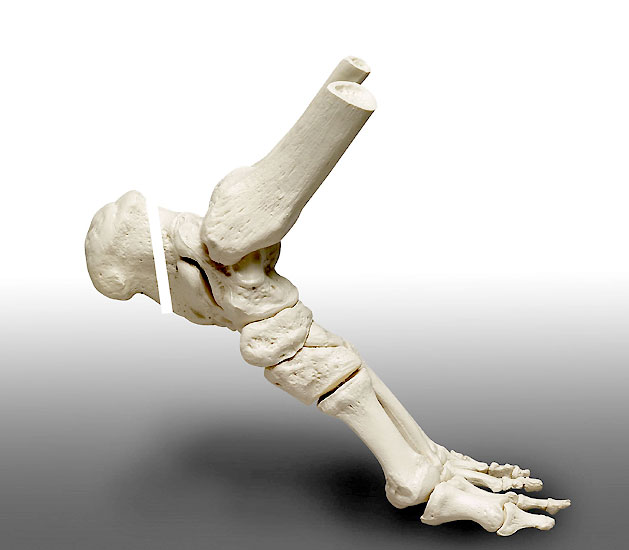

Wir mehr Sehnenmaterial benötigt, kann durch einen zusätzlichen Hautschnitt in Höhe des Chiasma flexorum die Sehne des M. flexor hallucis longus und die Sehne des M. flexor digitorum longus dargestellt werden 9. Wird ein Redonschlauch dorsal am Sprunggelenk in die Sehnenscheide des M. flexor hallucis longus geschoben, kann der Verlauf der Sehnen palpatorisch gut identifiziert werden. Diese Technik erlaubt ein Absetzen der Sehne proximal des Chiasmas über eine kleine Inzision. Beim Absetzen der Sehne des M. flexor hallucis longus ist darauf zu achten, dass sämtliche Querverbindungen der beiden Sehnen vom Stumpf abgelöst werden, damit ein problemloses herausziehen aus dem Tarsaltunnel gelingt 10. Diese Technik ermöglicht eine langes Transplantat entweder in den distalen Achillessehnenstumpf einzuflechten oder über eine Querbohrung durch den Kalkaneus zu ziehen und mit sich selbst zu vernähen (Abbildung 13)

Langer Sehnenstumpf, der über eine Querbohrung durch den Kalkaneus gezogen wurde und mit sich selbst vernäht werden kann.

Abbildung 13

Die Autoren verwenden inzwischen ausschließlich den dorsalen Zugang 11. Da der Muskelbauch des M. flexor hallucis longus bis zur Eintrittsstelle in den Kalkaneus zieht, ersetzen Muskel und Sehne zusammen die Achillessehne. Insgesamt ist die transponierte Sehne mit Muskelbauch etwas dicker als die ursprüngliche Achillessehne. Da ein 4 cm langer Sehnenstumpf für eine stabile Verankerung im Kalkaneus ausreichend ist, sehen wir keinen Vorteil in einem längeren Transplantat. Auch die Arbeiten von Tashjian et al. (2003) der an Leichenpräparaten die Festigkeit beider Fixationsverfahren verglich, konnte keine mechanische Überlegenheit einer der beiden Techniken feststellen 12.